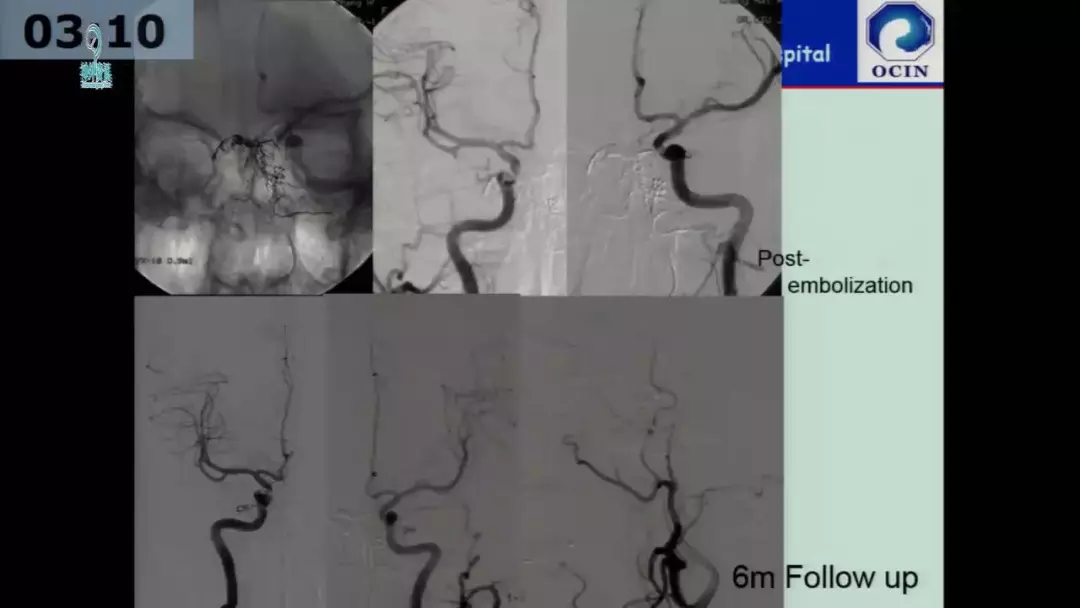

许奕教授:海绵窦区脑膜动静脉瘘的介入治疗